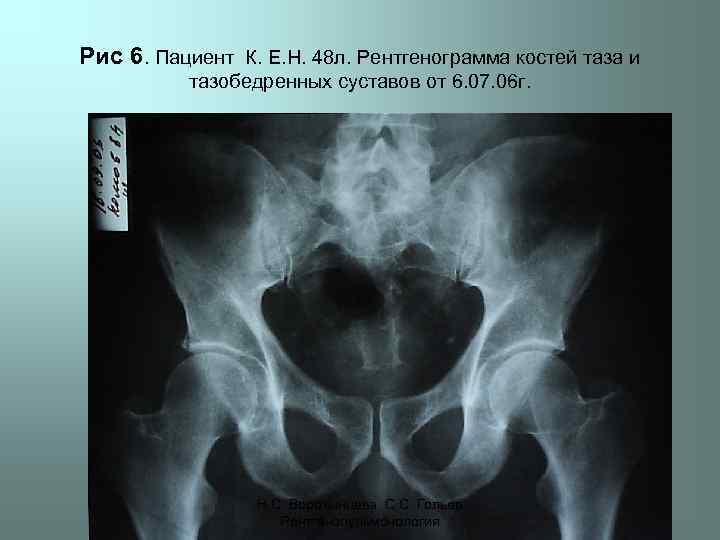

Рис 6. Пациент К. Е. Н. 48 л. Рентгенограмма костей таза и тазобедренных суставов от 6. 07. 06 г. Н. С. Воротынцева. С. С. Гольев Рентгенопульмонология